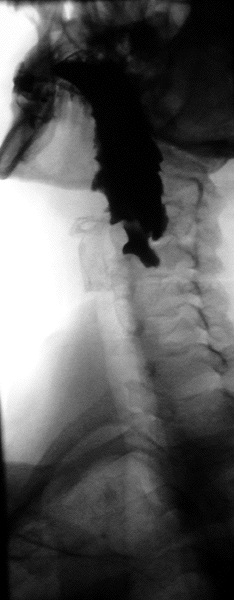

A Zenker's diverticulum, also pharyngoesophageal diverticulum, also pharyngeal pouch, also hypopharyngeal diverticulum, is a diverticulum of the mucosa of the pharynx, just above the cricopharyngeal muscle (i.e. above the upper sphincter of the esophagus). It is a pseudo diverticulum (not involving all layers of the esophageal wall).

In simple words, when there is excessive pressure within the lower pharynx, the weakest portion of the pharyngeal wall balloons out, forming a diverticulum which may reach several centimetres in diameter.

More precisely, while traction and pulsion mechanisms have long been deemed the main factors promoting development of a Zenker's diverticulum, current consensus considers occlusive mechanisms to be most important: uncoordinated swallowing, impaired relaxation and spasm of the cricopharyngeus muscle lead to an increase in pressure within the distal pharynx, so that its wall herniates through the point of least resistance (known as Killian's triangle, located superior to the cricopharyngeus muscle and inferior to the inferior constrictor muscles). The result is an outpouching of the posterior pharyngeal wall, just above the esophagus.[3]

The simple barium swallow will normally reveal the diverticulum. It may also be found with upper GI endoscopy, or CT with oral contrast.